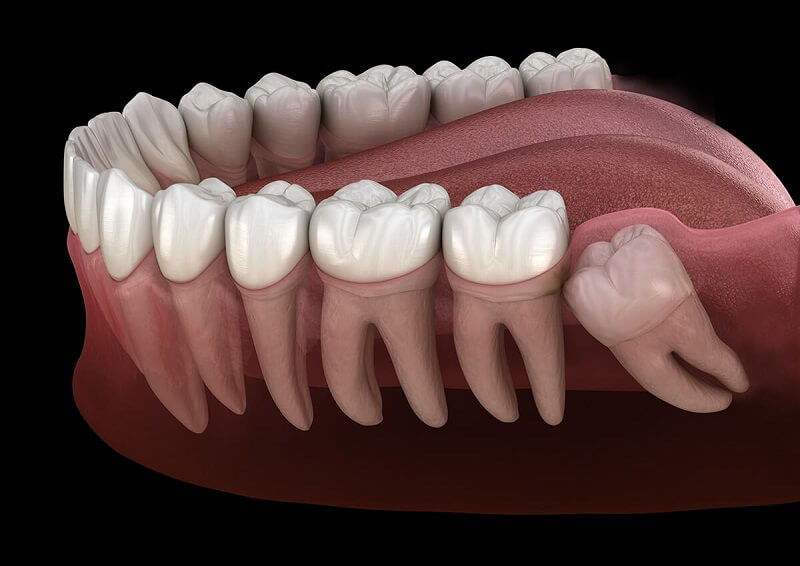

Trong quá trình tiến hóa vài triệu năm của loài người bắt đầu từ vượn cổ, xương hàm của con người trở nên nhỏ dần nên không đủ chỗ cho răng khôn mọc bình thường. Đạc biệt ở người châu Á, kích thước xương hàm nhỏ nên rất ít trường hợp răng số 8 mọc thẳng bình thường. Do đó răng khôn thường mọc lệch hoặc mọc ngầm, gây ra nhiều biến chứng nghiêm trọng.

Do xuất hiện muộn, trải qua quá tình phát triển đầy đủ chân răng, rất nhiều răng khôn mọc không thuận như nằm ngược về phía xương hàm, đâm thẳng về phía răng bên cạnh (răng cối lớn thứ hai hay răng số 7) hoặc mọc kẹt, hay răng nhú được lên khỏi nướu được một phần thì dừng và ngừng mọc vĩnh viễn.